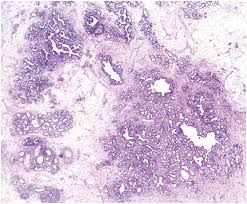

A large hamartoma of the spleen. Multiple hamartomas throughout the body occur in cowden's disease. A description of popcorn calcification—meaning images that look like popcorn on a ct. Endobronchial hamartoma resected by rigid bronchoscope. A mass resembling a tumor that represents anomalous development of tissue natural to a part or organ rather than a true tumor. Most isolated hamartomas are benign but in cowden's disease there is a risk that one or more may undergo malignant change.4. High magnification shows the 3 components of fhi. Report of two cases and comprehensive review of the literature.

The hamartoma is the dark circular object on the left that dominates the image. A rare cause of bronchial occlusion. High magnification shows the 3 components of fhi. May have recurrent genetic translocations. Meaning of hamartoma medical term.

Fibrous hamartoma of infancy with myxoid stroma.

A hamartoma is a benign, focal malformation that resembles a neoplasm in the tissue of its origin. A rare cause of bronchial occlusion. There is prominent myxoid stroma within the nodules. Jump to navigation jump to search. Hamartoma is a benign (not cancer) growth made up of an abnormal mixture of cells and tissues normally found in the area of the body where the a lesion first described by german pathologist eugen albrecht in 1904, hamartomas are generally benign tumors that may occur in the lungs, skin. A description of popcorn calcification—meaning images that look like popcorn on a ct. A large hamartoma of the spleen. This is not a malignant tumor, and it grows hamartomas, while generally benign, can cause problems due to their location. Breast hamartomas are responsible for roughly 5 percent of benign breast masses. A mass resembling a tumor that represents anomalous development of tissue natural to a part or organ rather than a true tumor. Most isolated hamartomas are benign but in cowden's disease there is a risk that one or more may undergo malignant change.4. May have recurrent genetic translocations. Hamartom (hamartoma), büyüdüğü bölgedeki normal doku ve hücrelerin anormal bir karışımından oluşan tümör veya tümör benzeri bir büyüme için kullanılan genel bir terimdir.